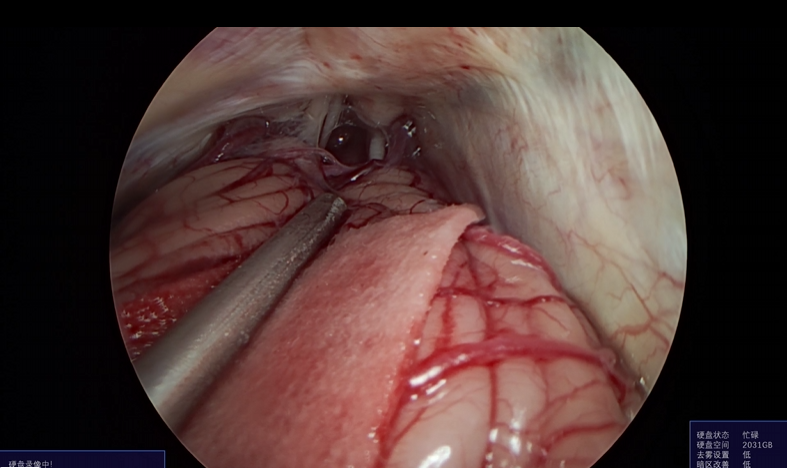

神经外科垂体瘤手术